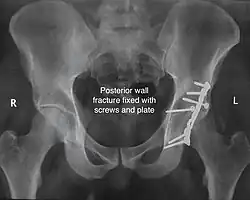

Posterior wall fracture fixed with screws and plate -

The final management depends on the size of the fragment(s), stability and congruence of the joint. In some cases traction for six to eight weeks may be the only treatment required; however, surgical fixation using screw(s) and plate(s) may be required if the injury is more complex. The latter treatment will be called for if bone fragments do not fall into place, or if they are found in the joint, or if the joint itself is unstable.